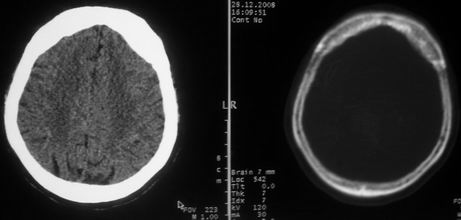

女,72岁,头晕。额骨有无问题。

额骨呈磨玻璃状增厚,考虑骨纤。

额骨呈磨玻璃状增厚,考虑骨纤

骨纤维组织异常增殖症又名纤维性骨炎,是一种以骨纤维变性为特点的骨胳系统疾病,是否为一真性肿瘤尚无定论。该病好友于儿童及青年,女性较多见,60%发生于20岁以前,偶见于婴儿和70岁以上老年人。男女发病为1∶2。80%以上表现为病骨区畸形肿胀;建议祥问病史,时间?